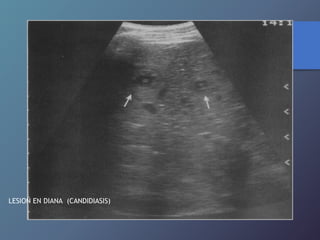

Enfermedades Micoticas

Hepáticas

• Infección secundaria hepática por diseminación

Hematógena de micosis sistémicas (cándidas).

• Inmunosuprimidos.

• Ecográficamente lesión en forma de ojo de toro

(Centro hiperecoico Y anillo hipoecoico), diámetro

De 1-4cm.

• Uniformemente hipoecoica (frecuente por fibrosis

Progresiva).

• Ecogena: calcificación variable por formación de

Cicatriz.

LESION EN DIANA (CANDIDIASIS)

Enfermedades Micoticas Hepáticas • Infecciónsecundaria hepática por diseminación Hematógena de micosis sistémicas (cándidas). • Inmunosuprimidos. • Ecográficamente lesión en forma de ojo de toro (Centro hiperecoico Y anillo hipoecoico), diámetro De 1-4cm. • Uniformemente hipoecoica (frecuente por fibrosis Progresiva). • Ecogena: calcificación variable por formación de Cicatriz.

LESION EN DIANA(CANDIDIASIS)